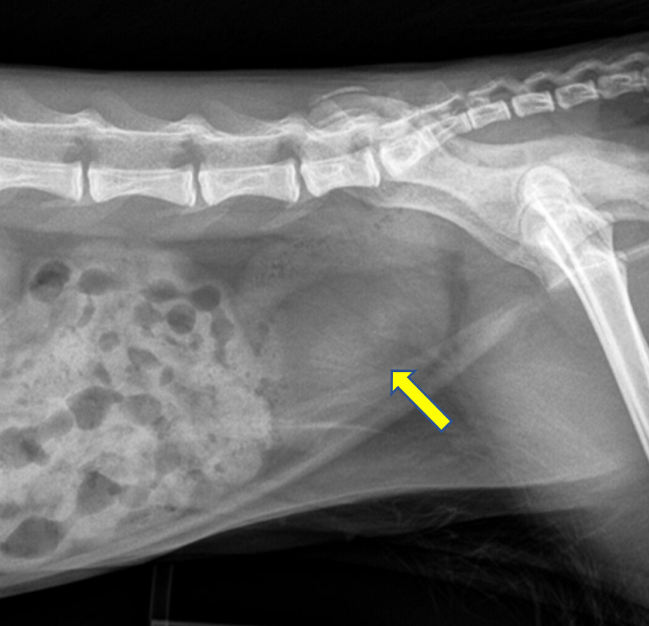

순도 98%의 GS-441524 로 구성된 결석이 발생한다는 것. 요로계 폐색까지 유발된 증례를 가지고 보고를 했으니 폐색 없이 발생한 증례도 상당할 것으로 예상된다.

결정의 변연이 이리도 날카로우니 당연히 물리적 자극에 의한 요로계 손상은 추정할 수 있을것.